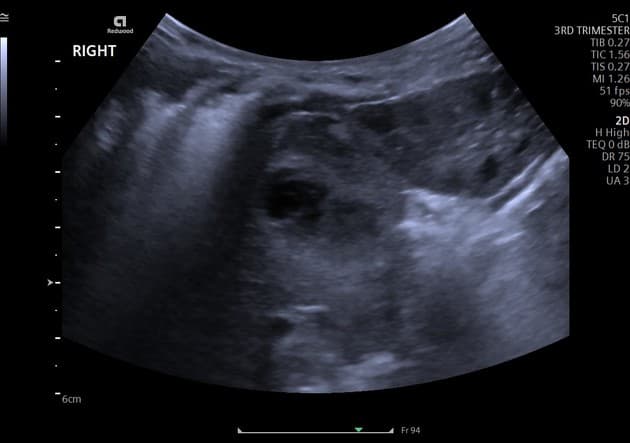

- Hạch to vùng cạnh động mạch chủ trái (bulky enhancing left para-aortic lymphadenopathy), có ngấm thuốc thì động mạch (arterial enhancement), kèm hoại tử trung tâm (central necrosis).

- Các nốt nhỏ ở cả hai cánh tuyến thượng thận trái, rất gợi ý di căn thượng thận (adrenal metastases).

Bệnh nhân đã cắt bỏ thận trái, nay hình ảnh cho thấy tái phát ung thư biểu mô tế bào thận (recurrence of renal cell carcinoma) dưới dạng di căn hạch cạnh động mạch chủ trái (left para-aortic nodal metastases).

Lưu ý rằng các di căn hạch (nodal metastases) này bắt thuốc tương tự đặc điểm tăng cường điển hình của ung thư biểu mô tế bào thận nguyên phát (primary renal cell carcinoma), với ngấm thuốc viền (peripheral enhancement) và hoại tử trung tâm (central necrosis).